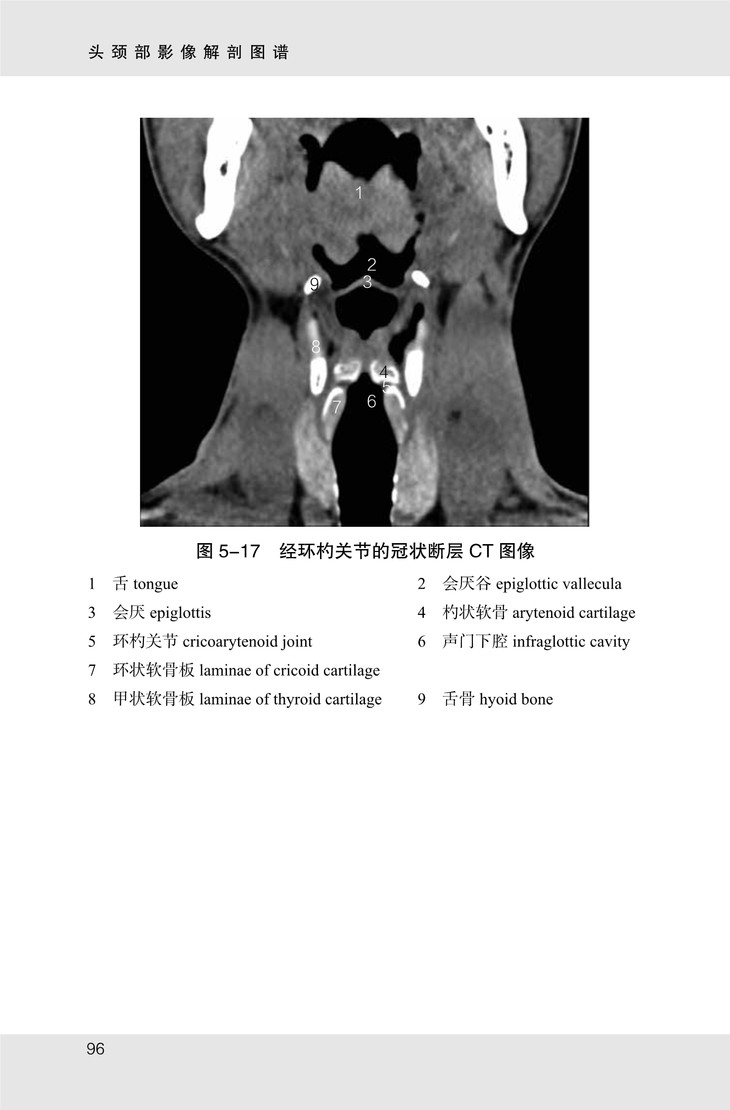

《头颈部影像解剖图谱》共包含眼眶、颞骨、鼻窦及喉部 CT 图像 107 幅,眼眶、内耳及颈部 MR 图像 70 幅。书中图像均来自山东省医学影像学研究所及济南市第三人民医院。MR 图像由 3.0T SIEMENS 磁共振扫描仪采集,序列包括 T1 加权像、T2 加权像;CT 图像由 SIEMENS 128层 CT 扫描仪采集,包括骨窗及软组织窗。

★ 内页插图 ★